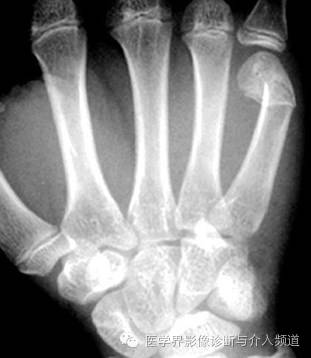

2、Skier’s掌骨

第1掌骨上缘慢性损伤。最早发现于苏格兰的猎场看守人。通常伴有掌指关节尺侧副韧带的损伤。急性损伤现在多称为“Skier’s tumb”,滑雪者摔倒时候由滑杆系带牵拉损伤所致。